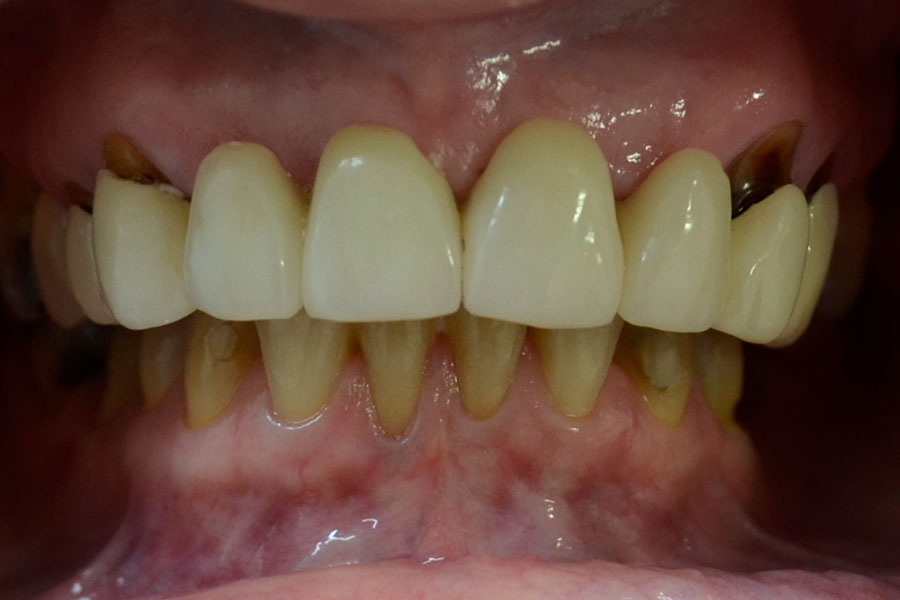

Simone has had a long span bridge to replace her missing four front teeth for over 30 years.

The admits that she never smiled confidently as the teeth did not look natural. The two teeth supporting the bridge on either side wore off around the gums due to the excessive stress from the long span bridge.

The bridge was removed and the four missing teeth in the middle were replaced with the support of two dental implants. The worn out supporting teeth were restored with individual crowns. It seems obvious that Jenni is quite confident with her new smile.